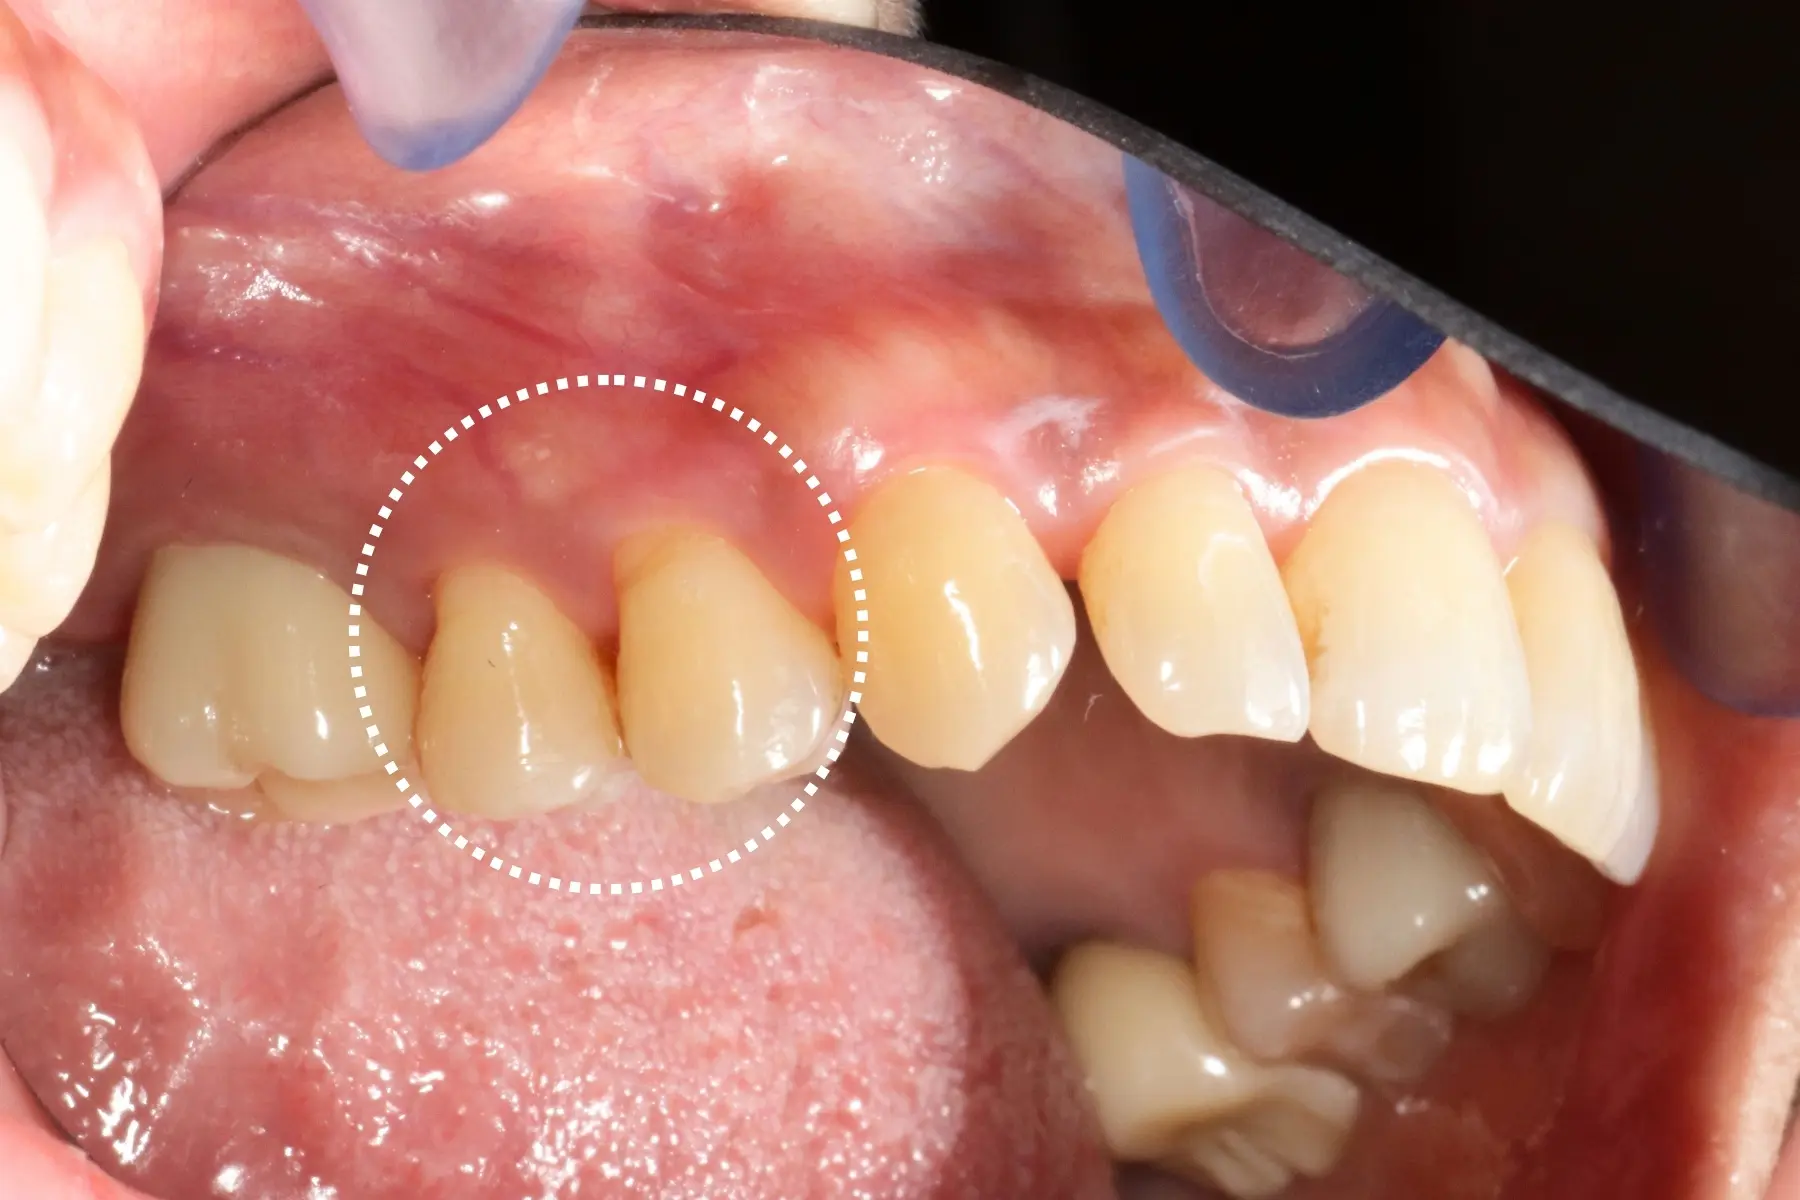

矯正完成下排前牙出現黑三角

• 術前 44

術後 42

仿生美學樹脂

主治醫師

• 陳暐文

治療時間

單次療程

主訴